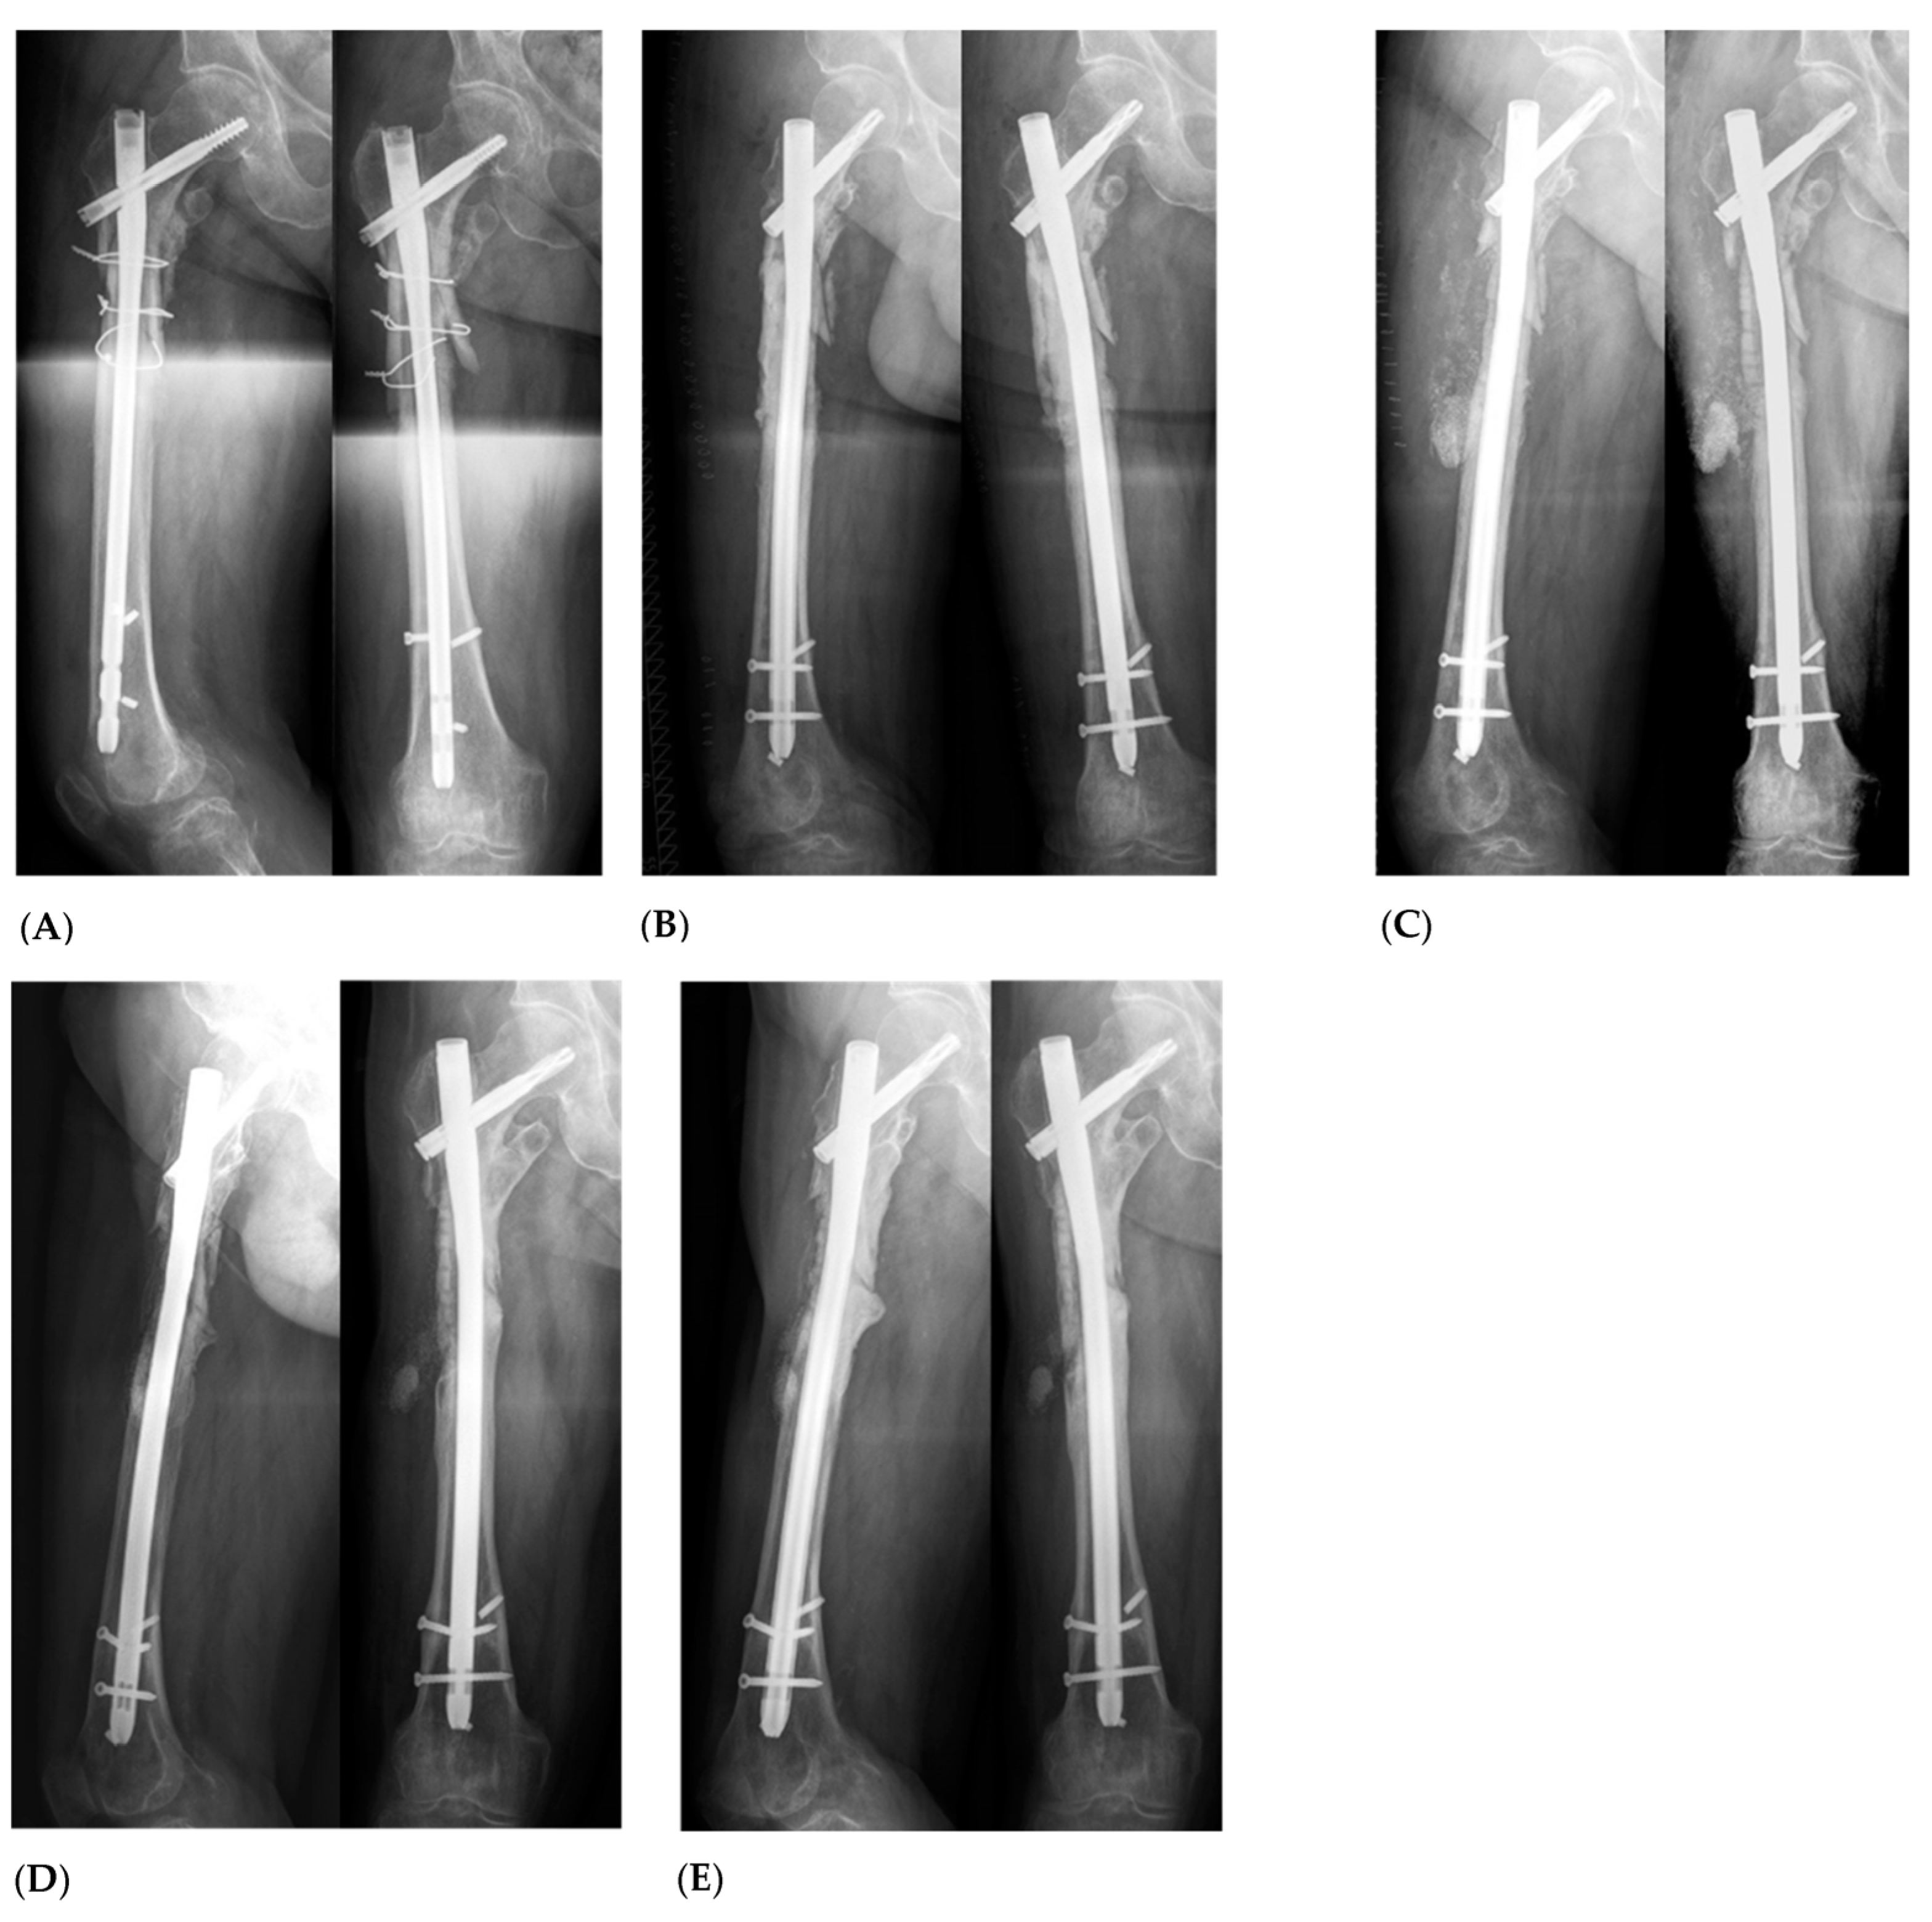

In order to address vascularization, all patients were treated with a two-staged induced membrane technique, first described by Masquelet A. in 2000 [11]. This procedure involves at least two operations. Figure 3 exemplifies the radiological follow-up of a study patient with a large size defect of the proximal femur (Figure 3).

Figure 3.

Case of a 55-year-old patient with atrophic nonunion following nail fixation of the proximal femur after subtrochanteric femur fracture (A). After performing Masquelet Step I with debridement of the atrophic bone, a significant bone defect exceeding 5 cm in size was observed (B). To address it, BaG was used as a bone substitute in combination with autologous bone using the RIA (Reamer Irrigator Aspirator) technique (C). At the 1-year follow-up (D), X-rays revealed complete bone consolidation, and ongoing bone remodeling was observed after 2 years (extended follow-up) (E).